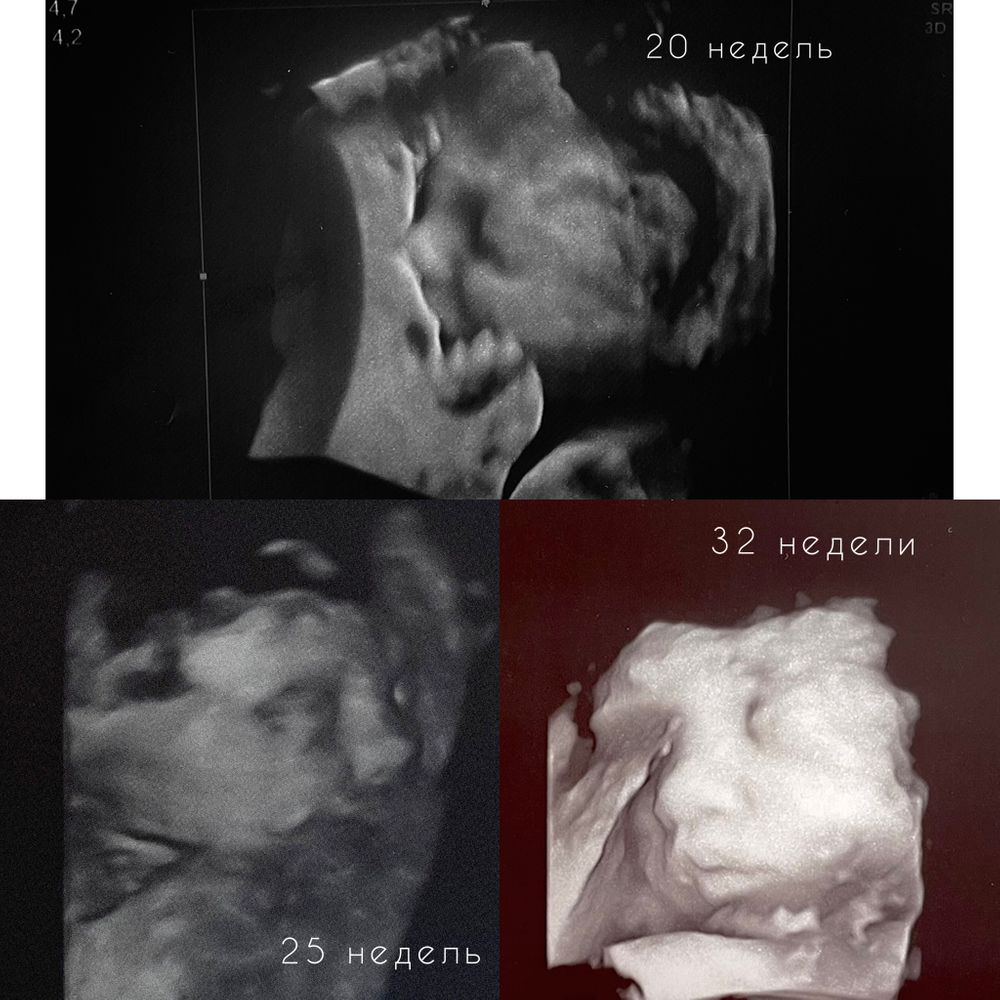

В 20 недель делала, сын был очень похож на себя новорожденного, но единственное был очень худой. А вот черты лица видно хорошо было. 3 скрининг не делала, просто обычное УЗИ в ЖК

Если прям детально посмотреть мордашку, то лучше конечно 30-32 недели. Заодно и 3 скрин пройдёте. В целом, картинка будет хорошая, но малыш ещё будет не очень похож тк он ещё жирочком и мяском обрастает. Ну и после 22 недель картинку в одной плоскости тоже не покажут уже. Уже большой)))